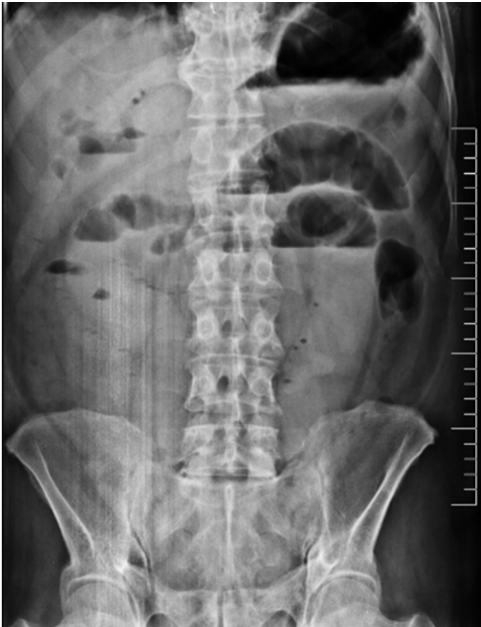

En dicha institución se revalora al paciente, evidenciando al examen físico mal estado general, consciente, orientado, con signos de dificultad respiratoria y desaturación al aire ambiente hasta 70%, saturación hasta 92% con oxígeno por máscara con reservorio a 8 l/min, piel y mucosas moderadamente secas, normocoloreadas, pulmones con murmullo vesicular disminuido con estertores y roncus diseminados en ambos campos pulmonares, abdomen levemente distendido, con ruidos hidroaereos (+) hipoactivos, blando, doloroso a la palpación profunda en mesogastrio, sin datos de irritación peritoneal, tacto rectal con esfínter normotónico, ampolla rectal vacía y dedo de guante explorador limpio, siendo el resto del examen conservado. Se obtienen estudios complementarios de laboratorios en sangre que reportan: leucocitosis de 10 640/ml, con neutrofilia del 88 %, Hb 12 g/dl (previo de 15,2), normocítica, normocrómica, Hto 34,8 %, hipoproteinemia con hipoalbuminemia severa con proteínas totales de 4,2 g/dl y albumina de 2,1 g/dl, e hipokalemia leve con K de 3,0 mEq/L, además de gasometría arterial que evidenciaba alcalosis metabólica parcialmente compensada con acidosis respiratoria, con insuficiencia respiratoria aguda hipoxémica moderada (PaFiO2 170), y resto de laboratorios del hemograma, coagulograma, glicemia, pruebas renales y hepatograma dentro de parámetros normales. Se obtiene a la vez Rx de tórax PA y abdomen AP de pie, evidenciando en el primero imágenes radiopacas de infiltrado alveolo-intersticial diseminadas en ambos campos pulmonares a predominio del lado izquierdo, y en la segunda, asas de intestino delgado dilatadas con imagen sugestiva de pila de monedas y niveles hidroaéreos a predominio del lado izquierdo (Figura 1). Tras la obtención de estos exámenes y en el contexto del paciente se han tomado en cuenta los diagnósticos diferenciales de obstrucción intestinal vs hemorragia digestiva alta, este último según la institución inicial que realizó la referencia, que indicaba la presencia de vómitos porráceos y el evidente descenso de la Hb en 3 puntos, por lo que se continúa con la indicación de endoscopia digestiva alta la cual reporta: “Datos de obstrucción intestinal alta (debito de retención proveniente de segunda y tercera porción duodenal) (Figura 2), sospecha de metaplasia columnar de esófago, gastritis crónica superficial de antro, estudio parcialmente satisfactorio (por segmentos con debito retentivo no valorables)”. Con estos hallazgos se refuerza mucho más la primera hipótesis, pero llama la atención que un paciente sin antecedentes quirúrgicos abdominales presente datos de obstrucción intestinal, además de tratarse de un paciente con un cuadro clínico atípico, y que al momento no había podido ser resuelto bajo medidas conservadoras, por lo que se decide solicitar estudios ampliados extrainstitucionales, como una tomografía axial computarizada (TAC) de abdomen con contraste de forma urgente; tras gestionar la misma, se obtiene reporte que indica (Figuras 3 y 4): “Hallazgos tomográficos compatibles con íleo biliar (imagen de cálculo de 4 x 3,2 cm con áreas de calcificación en su pared a nivel de yeyuno proximal), probable fístula bilio-digestiva (colecistoduodenal), neumobilia, pequeños quistes renales simples bilaterales, hallazgos de la porción valorable de tórax sugerente de proceso infeccioso de etiología viral sugestivas de COVID-19”. Con ello se solicita la valoración por el servicio de cirugía que, en misma fecha de ingreso, realiza procedimiento quirúrgico de laparotomía exploradora, enterotomía, extracción de cálculo y enterorrafia, con diagnóstico postoperatorio de “Obstrucción intestinal alta, íleo biliar, neumonía por SARS-COV2, hiperplasia prostática”, describiendo en los hallazgos operatorios un cálculo de aproximadamente 4 x 4 cm que ocupaba la totalidad de la luz yeyunal a +/- 60 cm del ángulo de Treitz.

En relación a los hallazgos imagenológicos, la imagen en pila de monedas sigue teniendo alto valor diagnóstico en patologías obstructivas del intestino delgado como es en el caso nuestro, al igual que menciona Carpio-Deheza G5 en su publicación de abdomen agudo quirúrgico. En mención a imagenología se recomienda una adecuada valoración de los estudios iniciales que en sospecha de íleo biliar podrían ayudar al diagnóstico y evidenciar la conocida Triada de Rigler, que hace mención de la conjunción en la radiografía de abdomen de pie de: neumobilia, asas de intestino delgado dilatadas y la visualización directa o indirecta de un cálculo en intestino delgado, y en ocasiones, el cambio de posición del lito en radiografías de control. En la revaloración del caso de nuestro paciente se evidencia dos de estos signos específicos, asas de intestinos delgado dilatadas y una tenue imagen sugerente de neumobilia, siendo el hallazgo de dos de los signos de la triada de Rigler patognomónicos de íleo biliar según Aguila-Gomez MV; es así, que el uso de ésta puede ayudar y prescindir de elementos no coste-accesibles en algunos casos8.